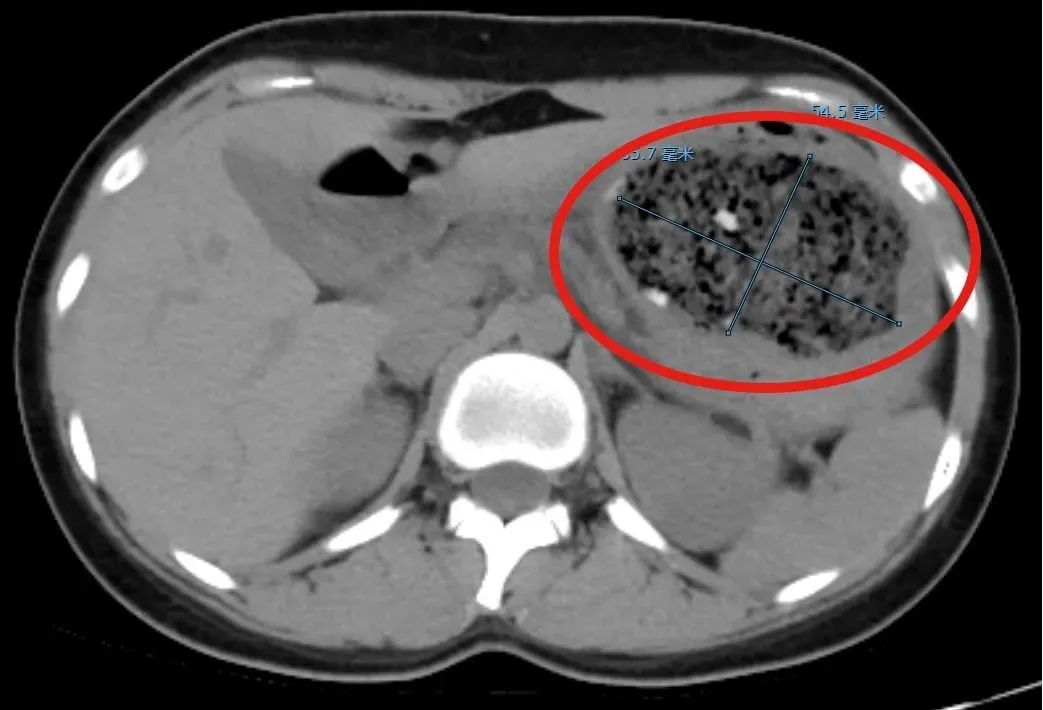

接诊的消化内科副主任杨晶简单问了病史后,给倩倩安排了腹部CT平扫检查,结果发现一个8.6cm×5.5cm左右的巨大的异物把她的胃塞得满满当当!

在进一步胃镜检查后,杨晶发现,倩倩胃里面的结石体积庞大,几乎不留什么空隙,这使得常规的异物圈套器无法施展。